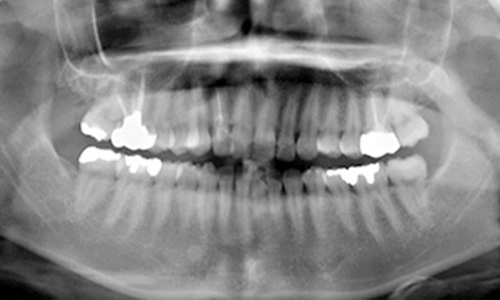

レントゲン写真では、はっきりとわかる歯槽骨の吸収は認められませんが、歯槽骨の硬い骨を表す白線が消えています。歯槽骨の頂点に線を引いていますが、ほぼ平行で一直線状を呈しています。